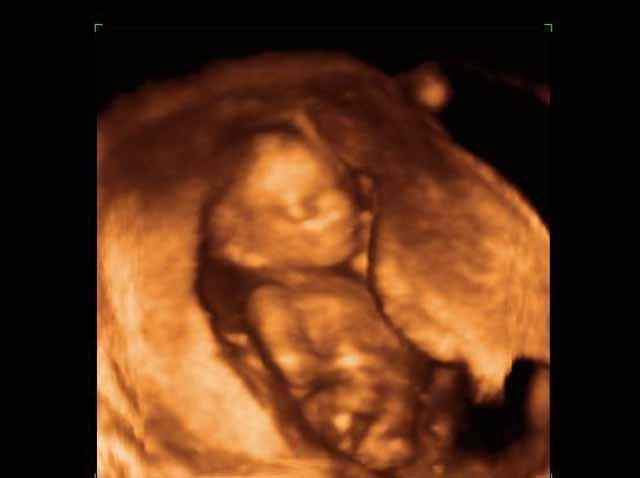

- Fetal Behavior Ultrasound Photos

Ultrasound Photos in 3D showing Fetal Behavior Inside the uterus | Dr N Layyous